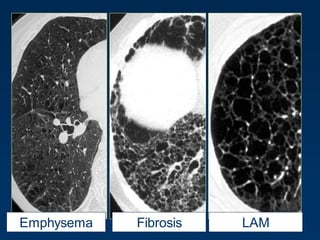

Cystic Changes and Decreased Density

Quiz

LAMEmphysema Fibrosis

LCHEmphysema

FibrosisEmphysema